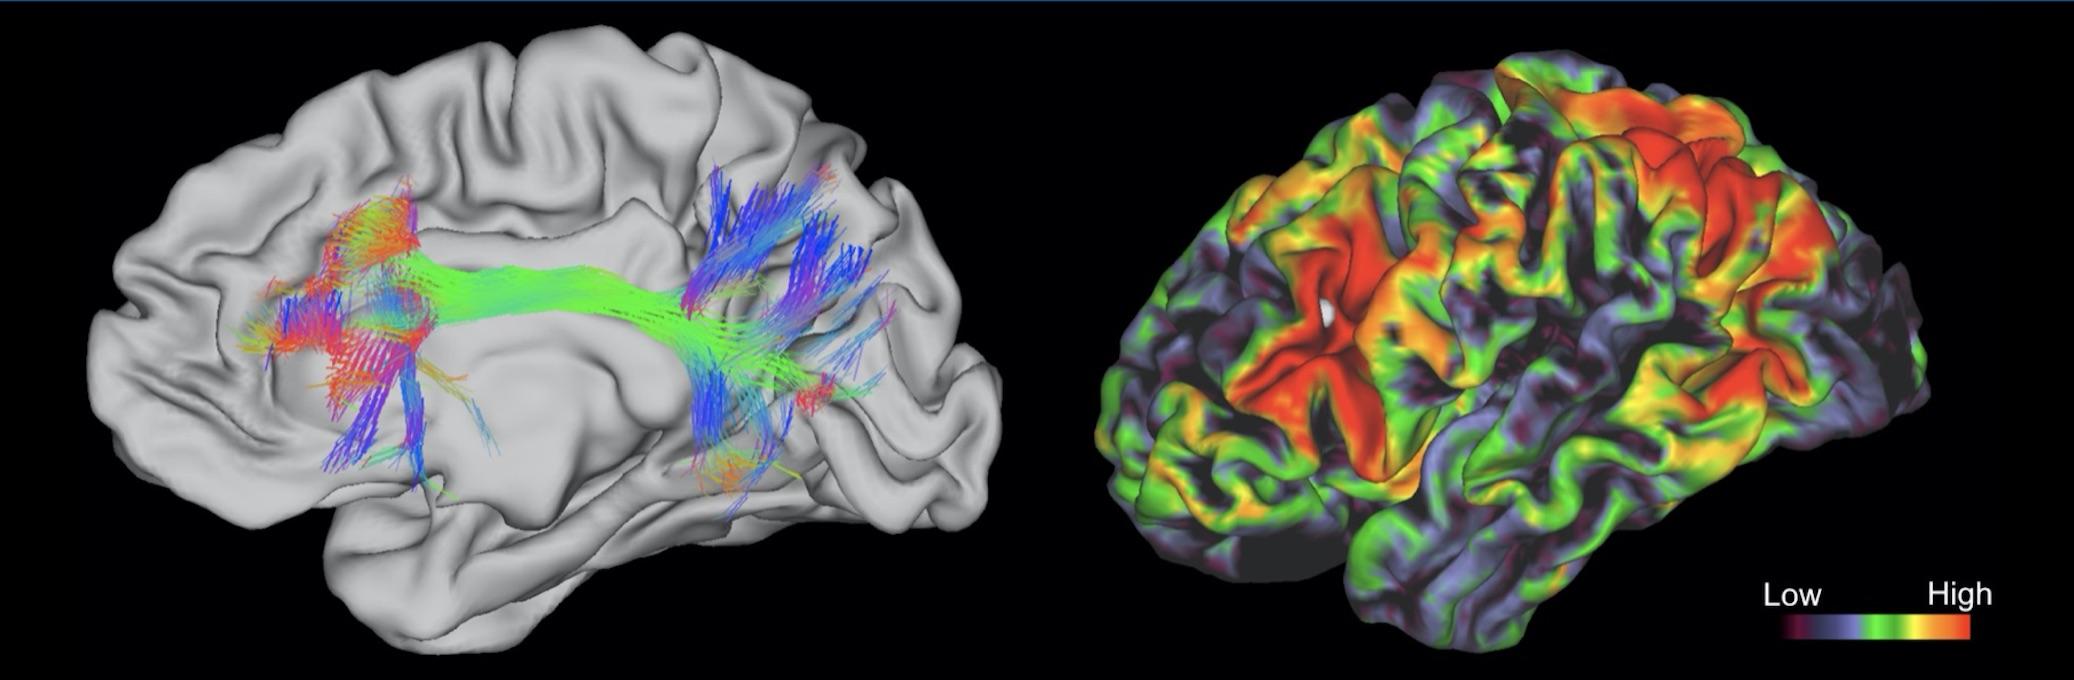

High-resolution EEG brain mapping

Machine learning–driven pattern recognition

Proprietary neurofeedback algorithms